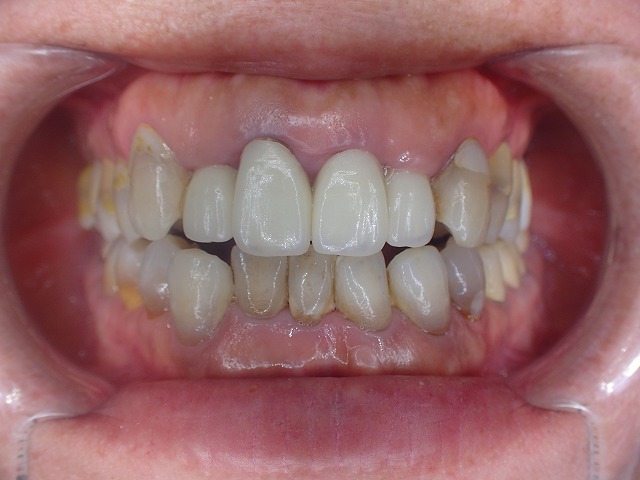

他院で制作したジルコボンドクラウンが

脱離したと来院されました。

20年以上も前の政策とのこと。

ややピンボケですがしっかりとした土台(コア)

が入っています。

透明度の高いジルコニアボンドクラウン。

透明度が高いので写真がピンボケ

外れたジルコボンドクランをセメント合着

当方の美観からするとちょっとねえ。。。

患者さんから20年以上前に

制作したものだとお聞きしました。

製作時は歯の先端はきちんと

左右対処であったのだと思います。